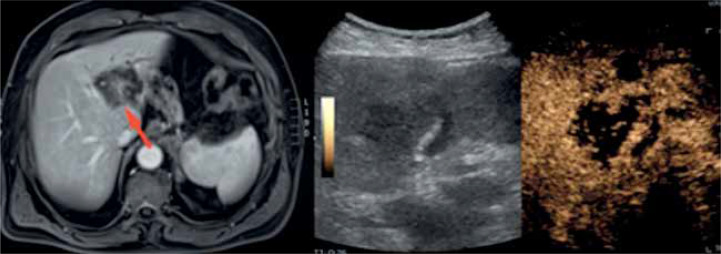

本研究的目的是确定对比增强超声(CEUS)在肝活检中的有用性。腹腔显像技术的普及,尤其是超声(USG),导致局灶性肝病变(FLL)的检出率增加。如果其他成像方式(磁共振成像[MRI]或计算机断层扫描[CT])的结果不确定,则应考虑经皮肝活检。考虑到在肝活检中使用MRI和CT的局限性,该程序主要是通过超声进行的。它经济、安全、快捷。无论何时,如果无法在b层显示病变(这是安全有效的活检所必需的条件),建议使用先进的超声技术-超声造影或融合成像。融合成像的局限性包括数据处理时间长,难以实现图像的最佳重叠。相反,超声造影增强病变的可视化,但没有上述限制-它是快速的,不需要额外的处理。此外,考虑到超声造影在肝局灶性病变的可视化和坏死区域的分化方面的潜力,以及检测神经内分泌肿瘤或其转移的能力,我们坚信超声造影辅助下的活检程序-特别是核心针活检-是当代诊断的有力工具。在本文中,我们想分享我们中心的经验,并回顾在超声造影指导下进行肝活检的现有文献。

The aim of this study is to determine the usefulness of contrast-enhanced ultrasound (CEUS) in liver biopsy. The popularisation of imaging techniques that visualise the abdominal cavity, especially ultrasonography (USG), has resulted in an increase in the detection of focal liver lesions (FLL). If the results of other imaging modalities (magnetic resonance imaging [MRI] or computed tomography [CT]) are inconclusive, percutaneous liver biopsy should be considered. Taking into account the limitations of using MRI and CT in liver biopsy, this procedure is mostly performed with ultrasound. It is economical, safe, and swift. Whenever it is impossible to visualise lesions in B-mode (a condition necessary for a safe and effective biopsy), it is advisable to use advanced ultrasound techniques - CEUS or fusion imaging. Limitations of fusion imaging include prolonged time of data processing and difficulties in achieving optimal overlap of images. Conversely, CEUS enhances lesion visualisation but is devoid of the mentioned limitations - it is rapid and requires no additional processing. Furthermore, considering the potential of CEUS in the visualisation of focal liver lesions and differentiation of necrotic areas, accompanied by the ability to detect neuroendocrine tumours or its metastasis, we strongly believe that biopsy procedures - especially core needle biopsies - with CEUS assistance are potent tools in contemporary diagnostics. In this paper we want to share the experience of our centre and review the available literature on performing liver biopsies under CEUS guidance.